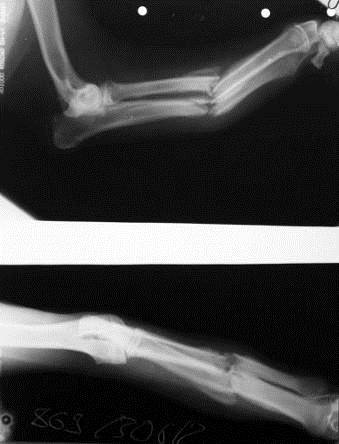

Рентгеновское исследование.

Проведённая рентген-диагностика выявила диафизарный перелом локтевой и лучевой костей левой грудной конечности.

Правильная диагностика вида, характера перелома дает предпосылки для проведения квалифицированного его лечения. Диагноз курируемому животному был поставлен на основании анамнестических данных (anamnesis morbi), визуального осмотра, бимануального исследования, рентгенографии.

На основании рентгенологической картины поврежденного сегмента, в двух стандартных проекциях, до операции, в зависимости от уровня перелома, собирается модуль аппарата. При повреждении средней трети предплечья аппарат состоит из четырех опор (дуга, 3 кольца); при переломах верхней и нижней трети - из трех опор (дуга, 2 кольца). В зависимости от длины предплечья, у мелких собак, используют две опоры (дуга, кольцо) и кронштейны.